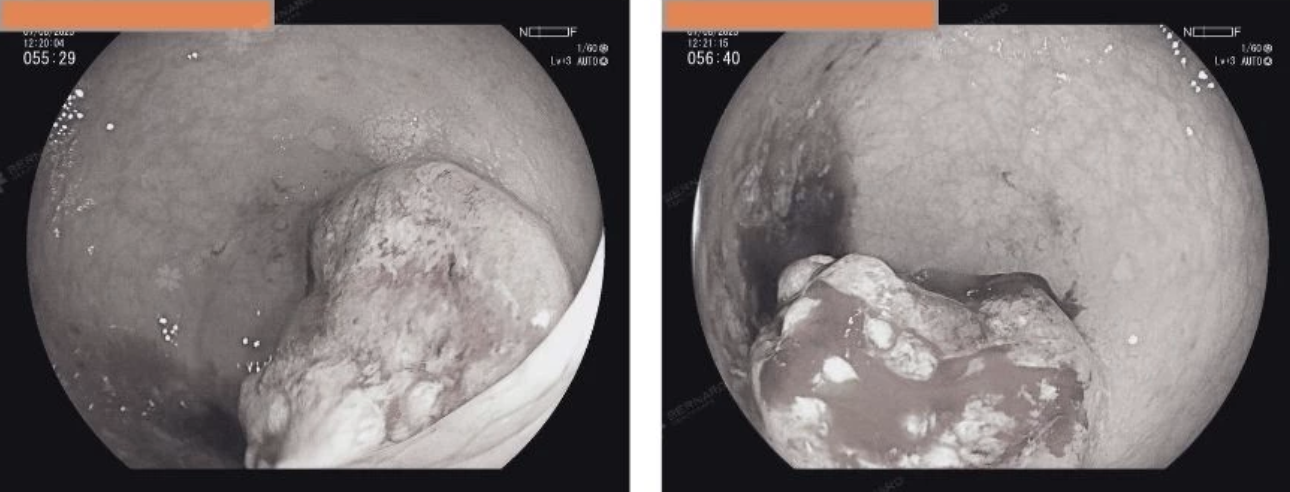

Nội soi cho thấy nhiều polyp dọc khung đại tràng đến trực tràng, gồm polyp có cuống, cuống ngắn và không cuống, kích thước từ 7 mm đến 20 mm. Theo phác đồ, các polyp lớn được cắt bỏ ngay trong quá trình nội soi.

Đáng chú ý, các bác sĩ còn phát hiện một khối u sùi ở trực tràng, cách bờ hậu môn 10 - 12 cm, kích thước khoảng 3 cm, lan theo chu vi lòng trực tràng, niêm mạc bở và dễ chảy máu, đặc điểm gợi ý nguy cơ ác tính cao. Toàn bộ tổn thương được sinh thiết và gửi giải phẫu bệnh để xác định chính xác bản chất.